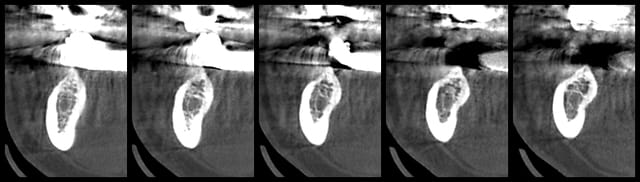

Patiente se présentant avec 6 implants posés depuis 4 ans en avant des 2 mentonniers, avec prothèse provisoire scellée suite à MCI.

Cette dernière veut réaliser une prothèse définitive mais les extensions(2 dents) étant trop importante, il y a trop de porte à faux, et le provisoire se descelle régulièrement.

Derrière il est possible de placer des implants de 4mm, les 6mm ne passent pas (crête fine).